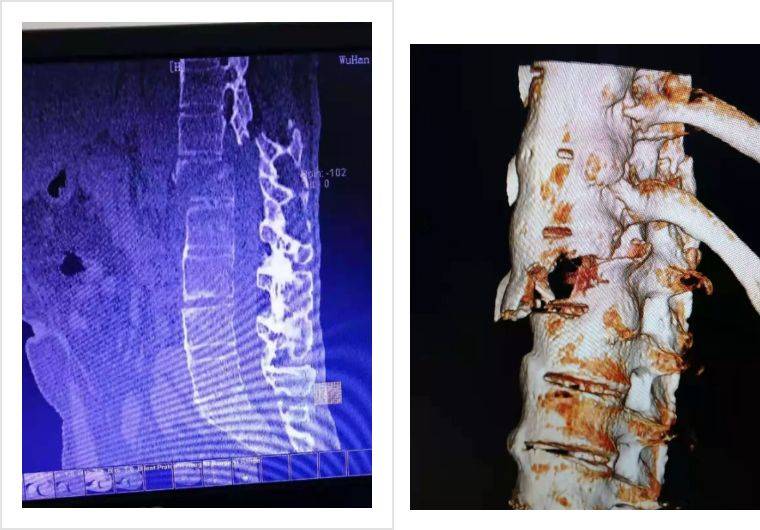

ct:颈4右侧椎板骨折,颈5-7椎体及椎板多发骨折

环枢关节ct 三维重建:c6双侧椎板骨折